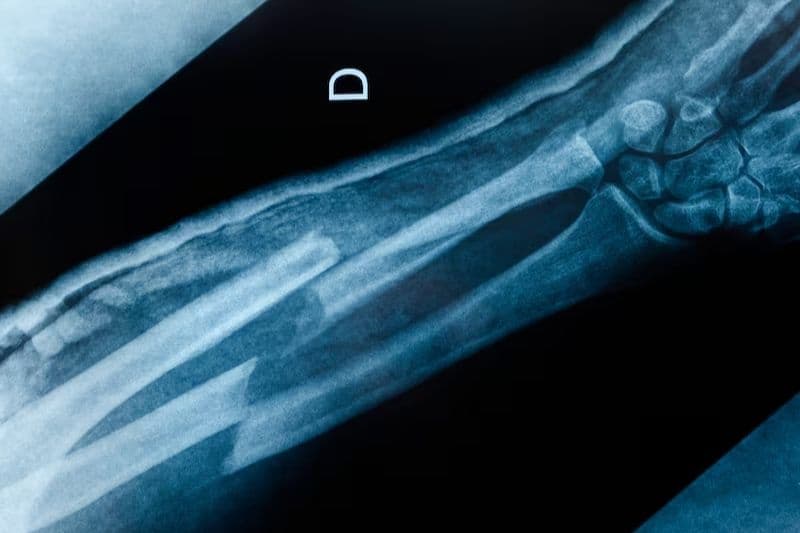

2.1. Gãy xương sau tuổi 50

Một trong những dấu hiệu điển hình của loãng xương ở người cao tuổi là gãy xương xảy ra sau những chấn thương rất nhẹ. Những vị trí gãy thường gặp gồm cổ tay, cổ xương đùi và các đốt sống vùng lưng hoặc thắt lưng. Trong đó, gãy cổ xương đùi là biến chứng nguy hiểm vì có thể làm giảm khả năng vận động và ảnh hưởng nghiêm trọng đến sức khỏe.